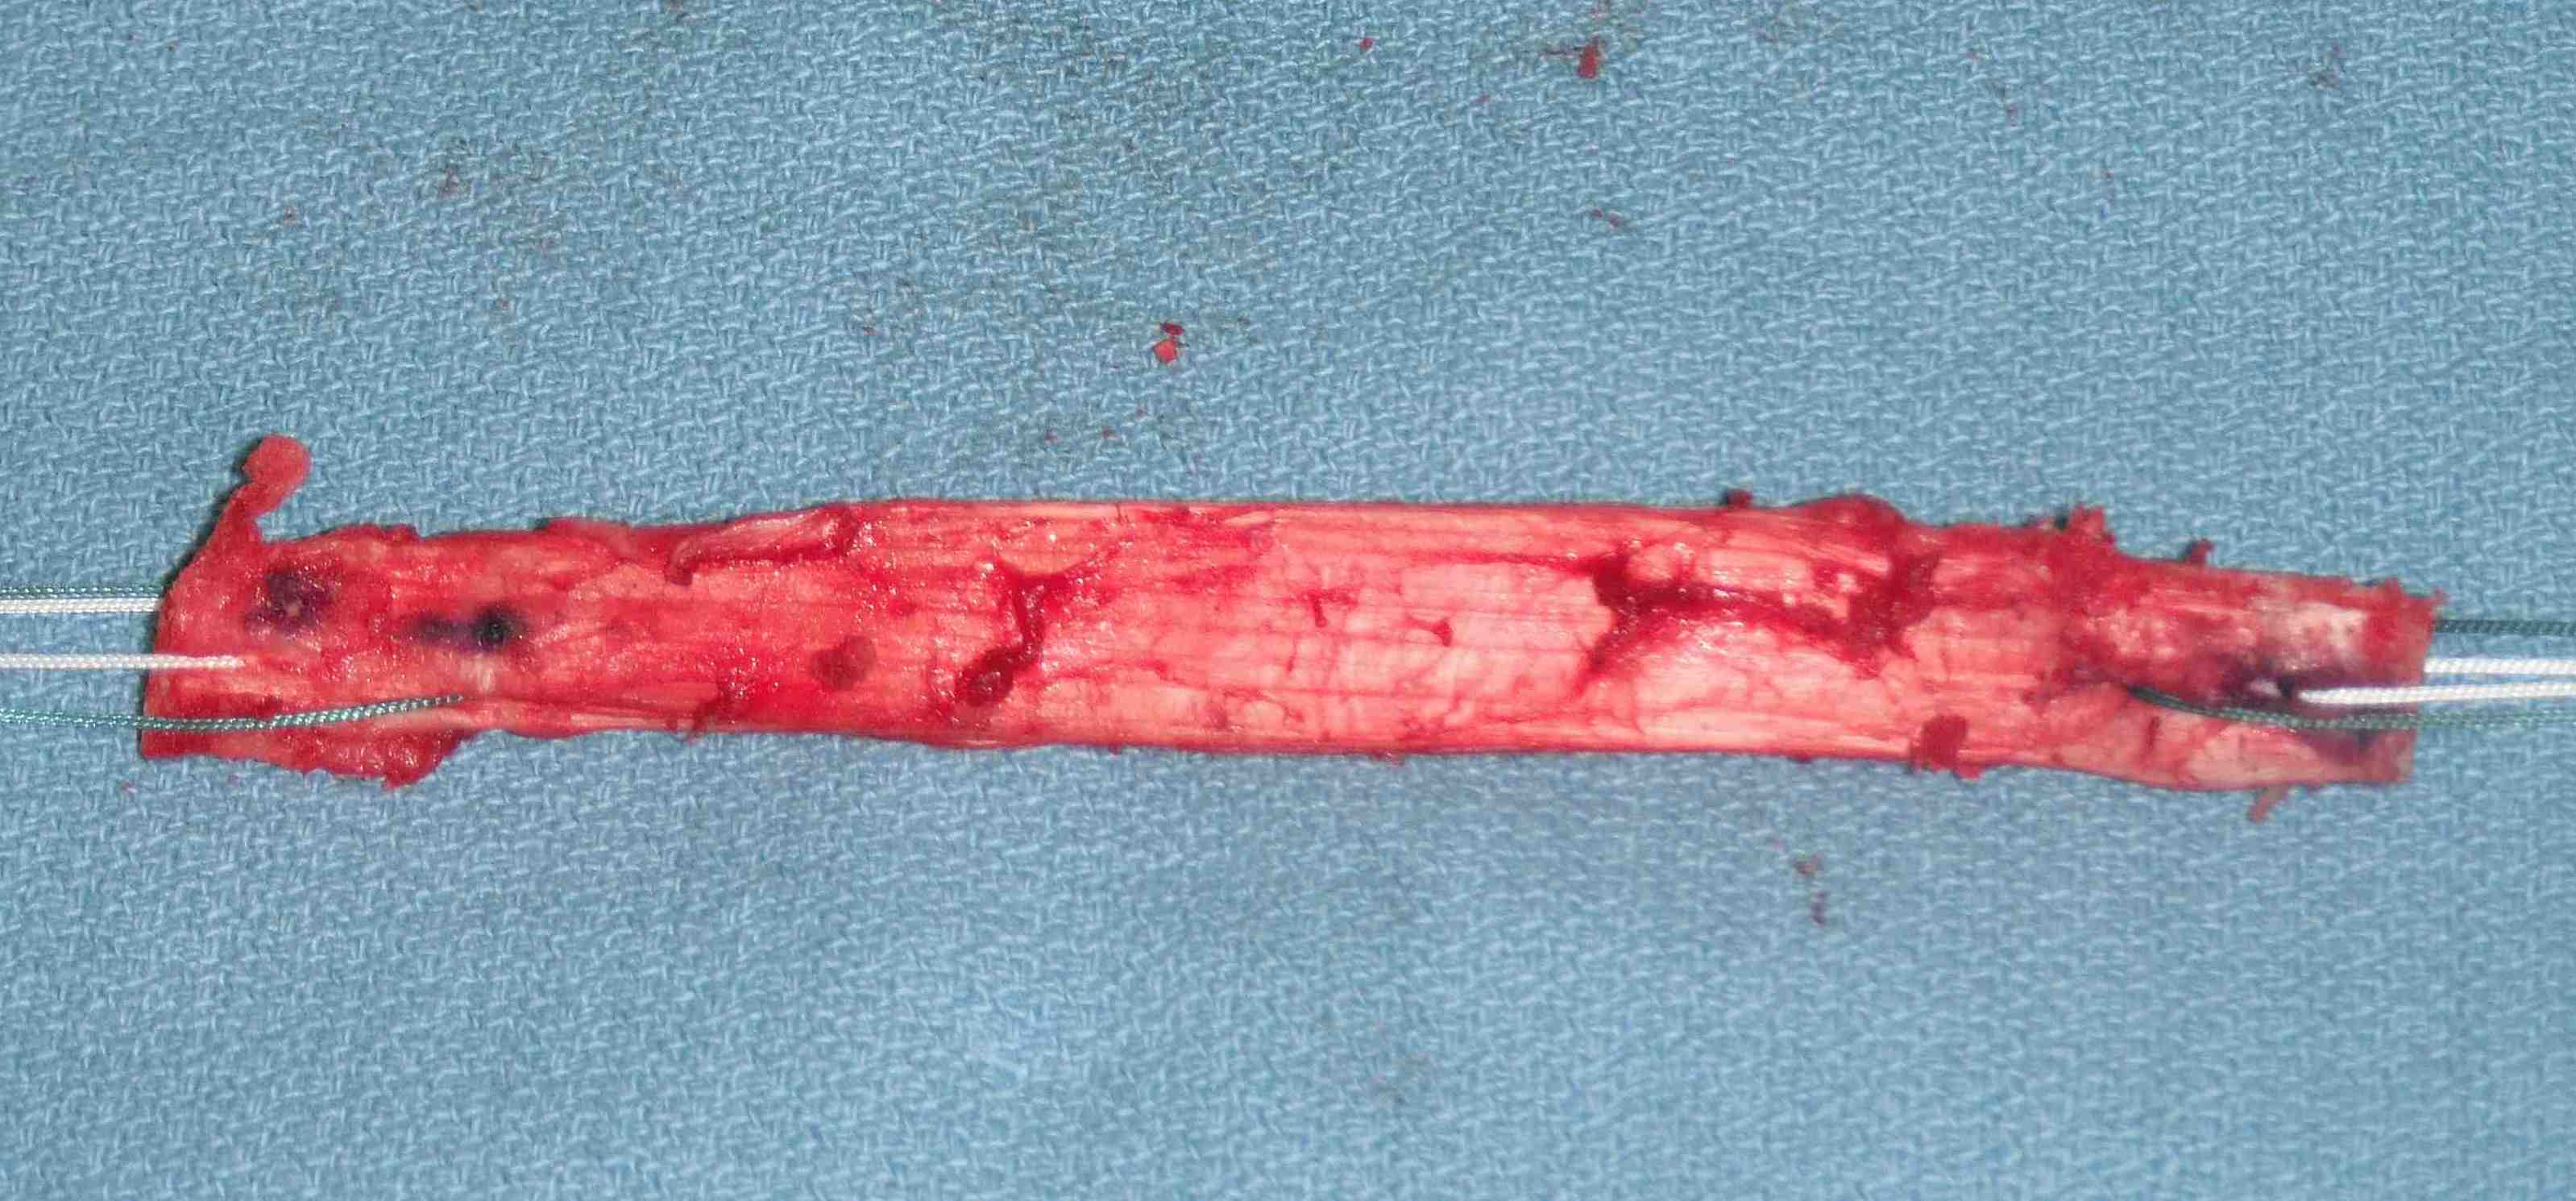

Graft preparation

Clean tendon of soft tissue

- decide which end will pass into femur

- usually the smaller piece

- nibble any sharp edges off especially on leading edge

- ensure whole graft will pass through 10 mm tube

- decide which end will be tibial or femoral

- mark femoral end with blue pen

- put 2 x 1 non absorbable sutures through drill holes

- probably don't need to tension BPTB